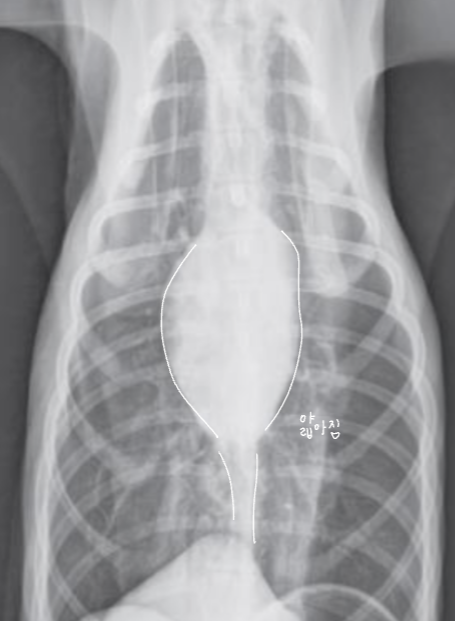

| CHF (Congestive Heart Failure, ์ธํ์ฑ ์ฌ๋ถ์ ) |

| 1) LCHF |

| LV โ LA โ Pulmonary vein hypertension โ lung โ PA |

| Radiographic signs - Pulmonary edema - PV enlargement - (cats) pleural effusion, patch alveolar pattern - LA enlargement (backpack sign, double wall sign) - alveolar pattern |

| 2) ==RCHF== |

| lung, PA โ RV โ RA โ CVC โ peritoneum |

| Radiographic signs - RA, RV enlargement - mPA bulging (reversed D) - Bilateral pleural effusion (interlobar fissure, scallop sign.. ๋ฑ) - Ascites, Edema, CVC dilation, Hepatosplenomegaly |